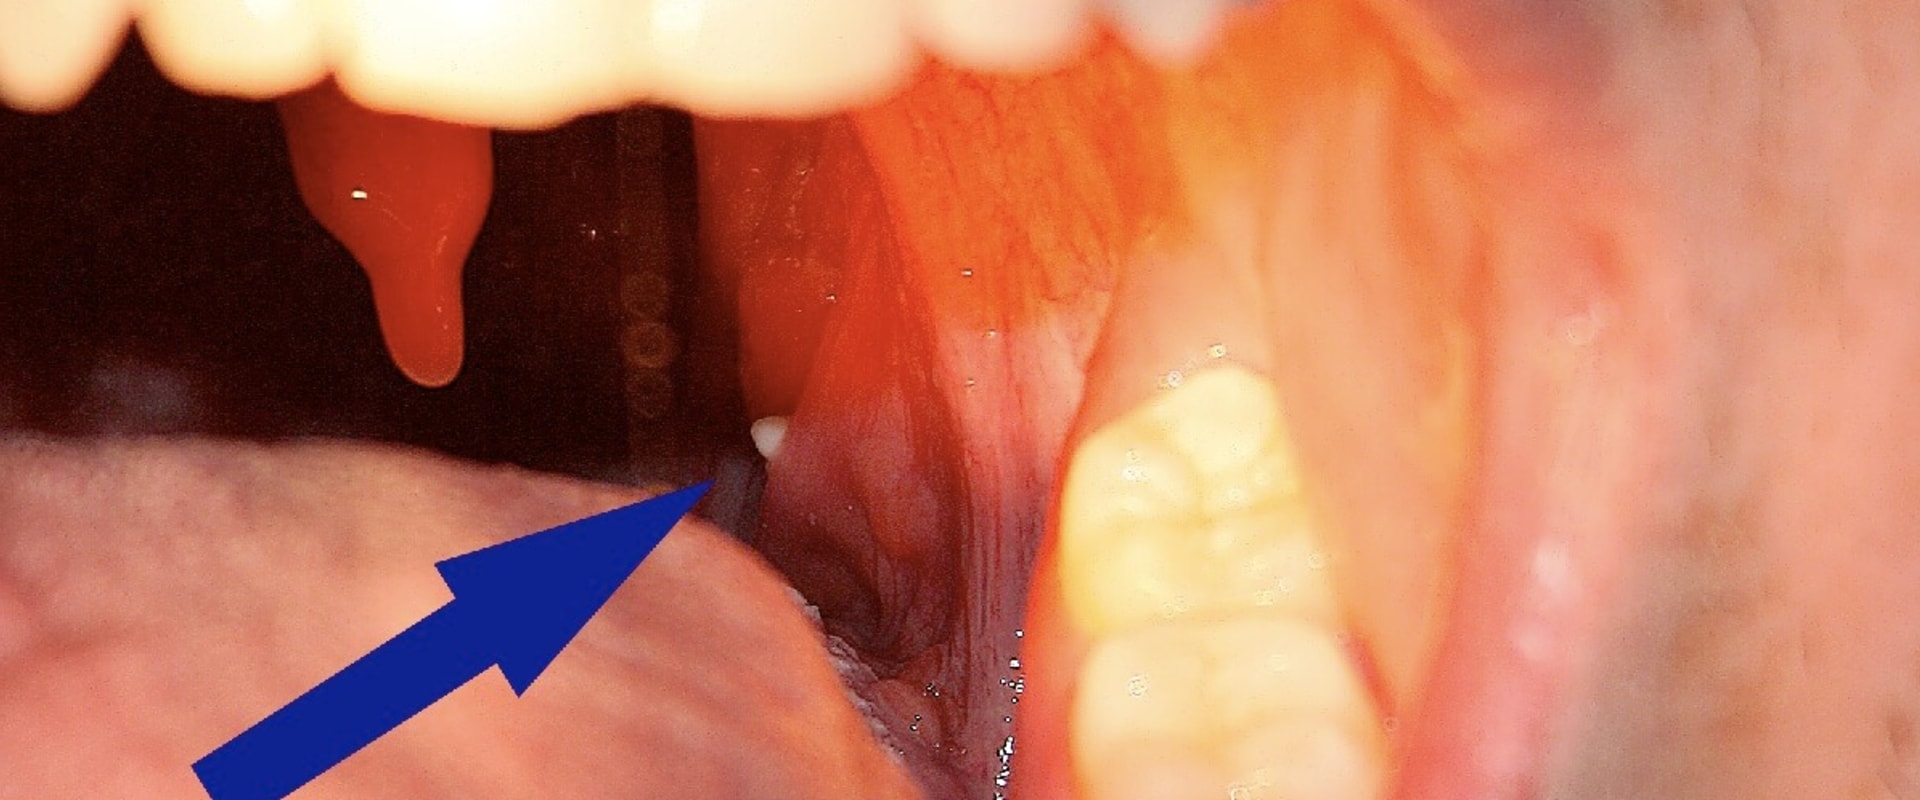

Can You Go To The Dentist With Tonsil Stones . you should see an ent healthcare professional for tonsil stones if your tonsils look red, bleed easily, or experience sore throat or ear pain. this is usually done if the tonsil stone is: In this article, we will explain. Talk with a doctor if they become a problem or you’re concerned about them. In fact, tonsil stones often fall out on their own eventually and the underlying cause. Here are some potential ways to. most people can use their tongue or a cotton swab to gently push against the tonsil to dislodge the stone. Tonsil stones are small, hard lumps that form on the tonsils’ surface due to a debris buildup. your tonsil stones can be surgically removed by a dentist, oral surgeon, or an ent specialist (for severe cases). if you have frequent tonsil stones, be sure to practice good dental hygiene and stay hydrated. Causing repeated bacterial infections and. you may not need to do anything if tonsil stones don’t bother you. These symptoms can develop after trying to remove or manipulate tonsil stones. However, in some cases, the tonsil. you can try to remove tonsil stones yourself or see your dentist or doctor if you have difficulty doing so.

Talk with a doctor if they become a problem or you’re concerned about them. Here are some potential ways to. if you have frequent tonsil stones, be sure to practice good dental hygiene and stay hydrated. your tonsil stones can be surgically removed by a dentist, oral surgeon, or an ent specialist (for severe cases). In fact, tonsil stones often fall out on their own eventually and the underlying cause. Causing repeated bacterial infections and. most people can use their tongue or a cotton swab to gently push against the tonsil to dislodge the stone. this is usually done if the tonsil stone is: Tonsil stones are small, hard lumps that form on the tonsils’ surface due to a debris buildup. In this article, we will explain.